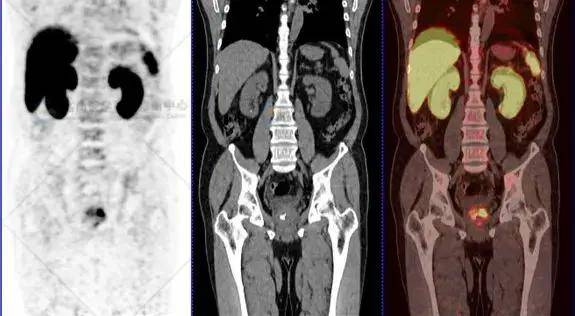

尿频2年多,psma pet/ct诊断前列腺癌